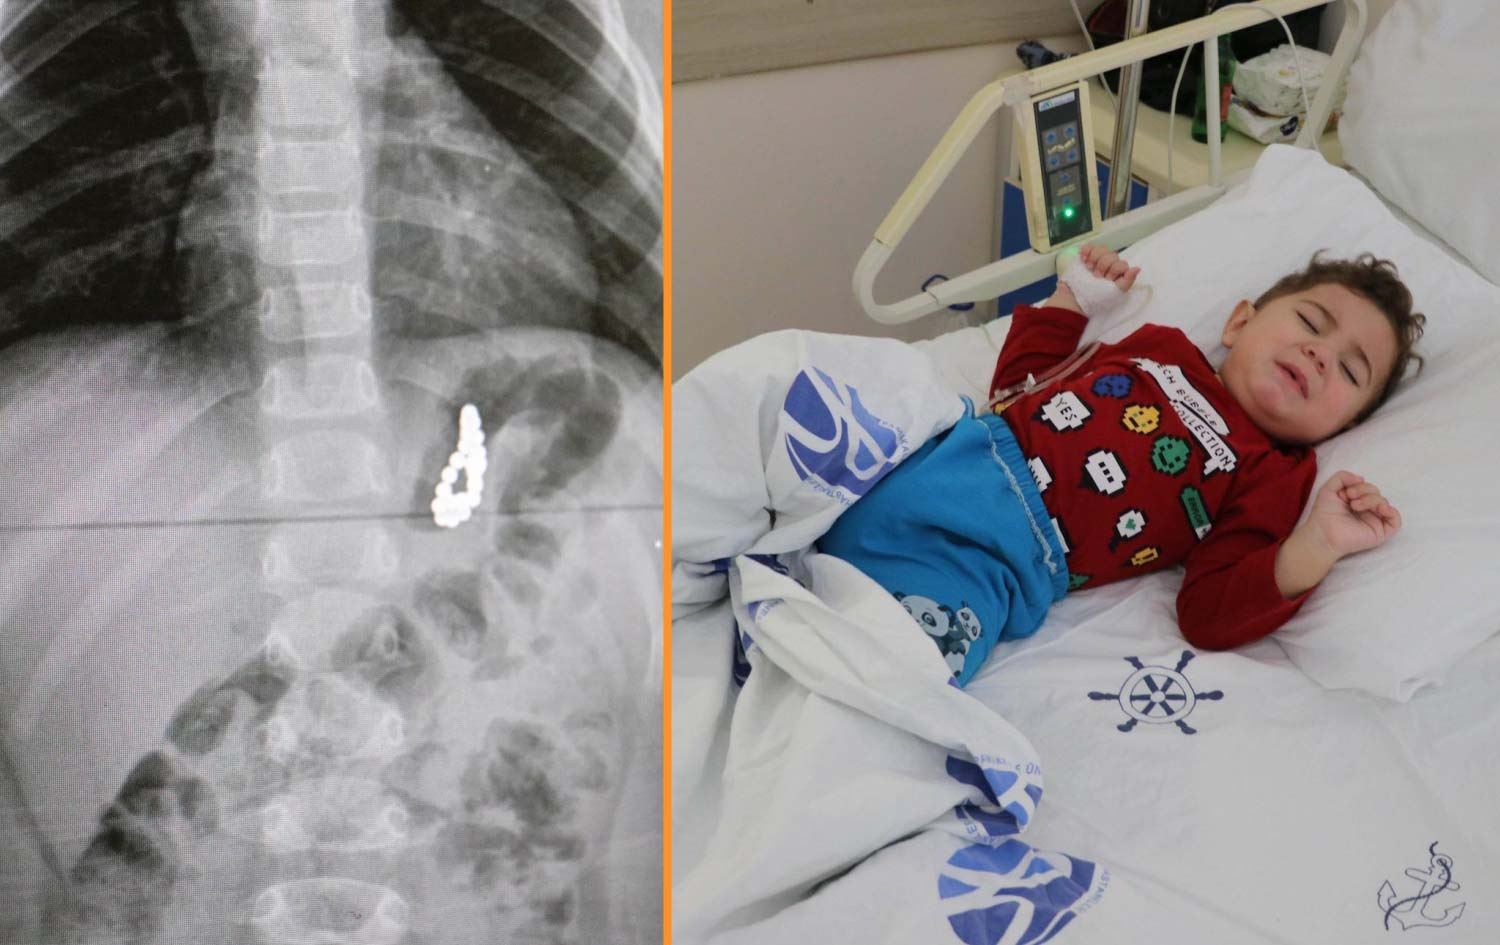

19 aylık bebeğin midesinden 17 adet mıknatıs çıkarıldı!